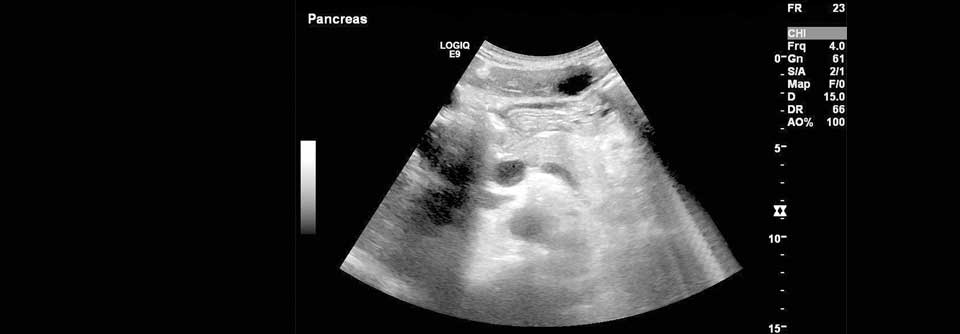

Eine neoadjuvante Chemotherapie ermöglicht auch bei Patienten mit Pankreaskrebs die Chance auf eine erfolgreiche (Teil-)Resektion. Eine neoadjuvante Chemotherapie ermöglicht auch bei Patienten mit Pankreaskrebs die Chance auf eine erfolgreiche (Teil-)Resektion. © Science Photo Library/Marazzi, Dr. P.

Dank einer vorangehenden Chemotherapie kann rund ein Drittel initial nicht-operabler Pankreaskarzinome doch noch entfernt werden. Die beiden Regime nab-­Paclitaxel und FOLFIRINOX scheinen dabei den Tumor ähnlich gut zu verkleinern. Den Bildbefund können Kollegen bei der Entscheidung für oder gegen eine Laparotomie eher vernachlässigen.